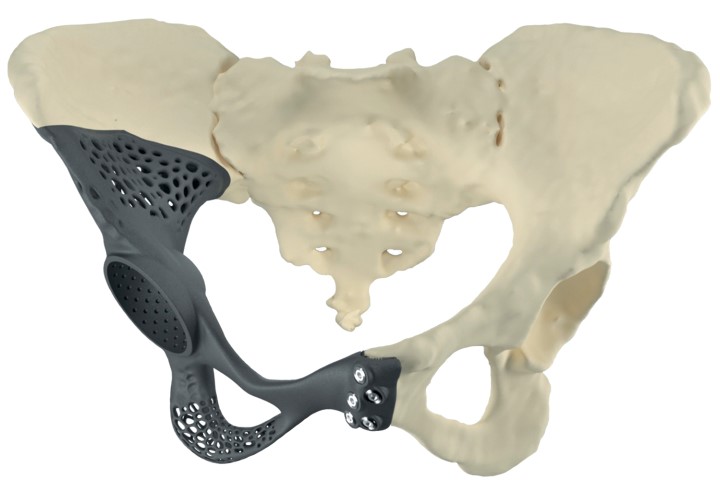

Приклад заміщення дефектів кісток тазу при ураженні пухлиною. Складне індивідуальне ендопротезування кульшового суглоба

Проектування та виготовлення індивідуальних аугментів для заміщення дефектів суглобів: М, 48р, асептична нестабільність онкологічного ендопротеза . Заміщення дефекту індивідуальним аугментом та ревізійним ендопротезом , фіксація БІС, ПММА